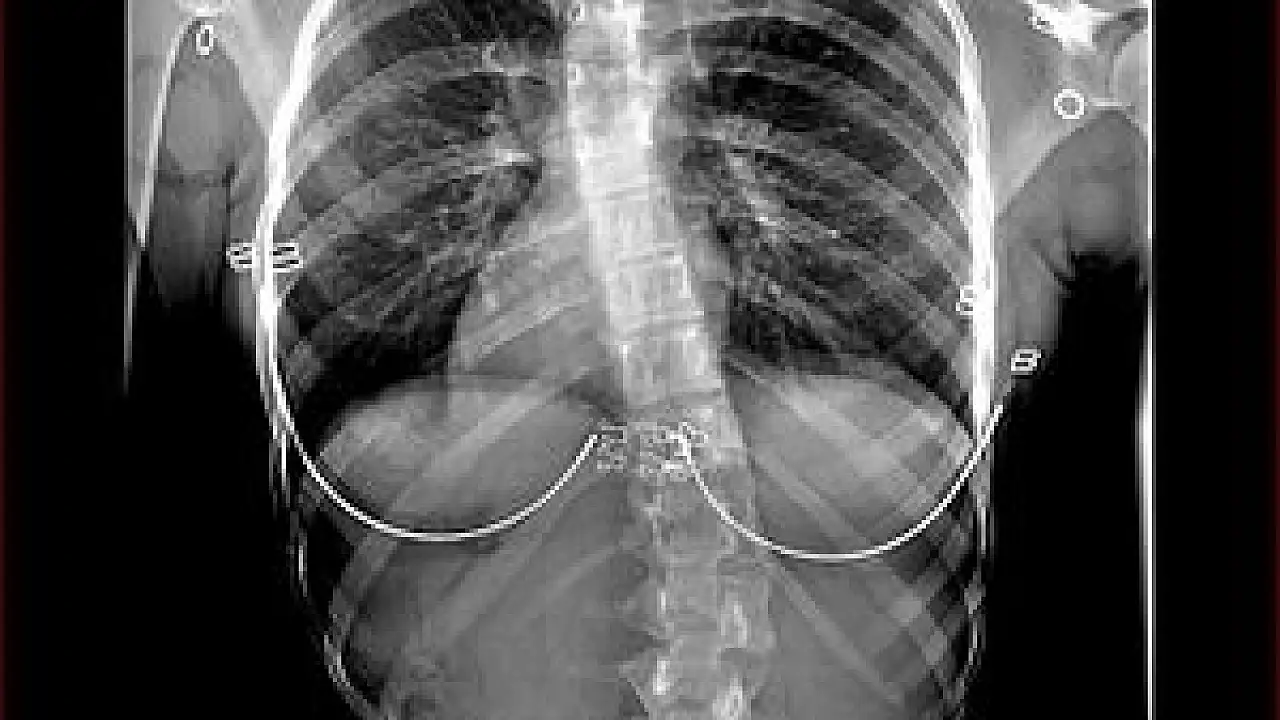

Ameliyattan önce özel eğilmeli ya da traksiyon filmi denilen özel röntgen filmleriyle skolyoz eğriliğinin ne düzeyde esnek olduğunun anlaşılmaya çalışıldığını sözlerine ekleyen Opr. Dr. Ulaş, “Ameliyatı yapacak olan cerrah bu filmlerle ölçüm yaparak esneklik hakkında fikir sahibi olur. Skolyoz eğriliği ne kadar esnekse, o kadar çok düzelme elde edilir. Skolyoz ameliyatından sonra iz kalmasını engellemek için cilt estetik dikiş kullanılarak dikilir. İz oluşumunu engelleyici kremlerin kullanılması ve ilk yıl güneşe çıkarken kesi hattının üzerinin örtülmesi kullanılan diğer önlemlerdir” diye konuştu.